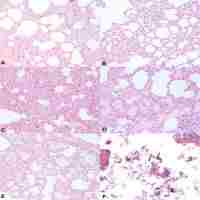

| Abstract | Objectives To evaluate the relationship between distributions of diatoms in lungs of drowned victims and in drowning medium using scanning electron microscopy, and to establish the diatom distributions in Pearl River's water bodies in Guangzhou urban area. Methods 10 white rabbits were drowned in the experiment, and the lungs of the rabbits as well as the drowning medium were collected; Moreover, the water samples of the six water bodies of Pearl River in Guangzhou urban area were collected in September (representing high-temperature months) and December (representing low-temperature months) of 2008 respectively; qualitative and quantitative analysis of diatom using scanning electron microscopy with automated scanning mode was performed for all the samples after being processed by microwave digestion and vacuum filtration. Results There was a concordance of the types and the relative abundance of each type of diatoms in the lungs compared to the site of drowning in 100% of the cases; and the diatom distributions in the six Pearl River's water bodies in Guangzhou urban area in September and December of 2008 were then developed. Conclusion The method using scanning electron microscopy with automated scanning mode for forensic diatom analysis has the advantage of labor saving and is capable of enhancing accuracy of qualitative and quantitative diatom analysis compared to the traditional method using light microscopy, thus is of prominent application value in forensic diagnosis of drowning. Diatom distributions in the lungs of drowned victims were closely related to drowning medium, therefore, the established diatom distributions of diatoms in Pearl River's water bodies in Guangzhou urban area will be very helpful in the diagnosis of drowning for bodies recovered in these water bodies. |